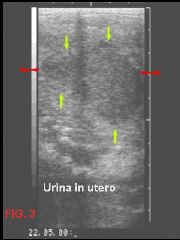

-         La porzione muscolare della cervice può essere ancora poco tonica, determinando una incompleta chiusura della stessa. Ciò creerebbe una porta d’ingresso ad agenti inquinanti come aria (FIG. 2), urina (FIG.3) o trasudati provenienti dall’infiammazione della parete vaginale che per gravità si depositerebbero sul fondo del vestibolo vaginale, proprio a contatto con lo sfintere cervicale (dopo il parto la massa dell’utero, ancora di dimensioni ragguardevoli, crea una inclinazione del vestibolo vaginale in senso postero-anteriore). Inoltre, lo stesso accoppiamento naturale, provocherebbe l’ingresso d’aria, attraverso la cervice, nell’utero, proprio per la scarsa capacità tonica della cervice nel richiudersi.